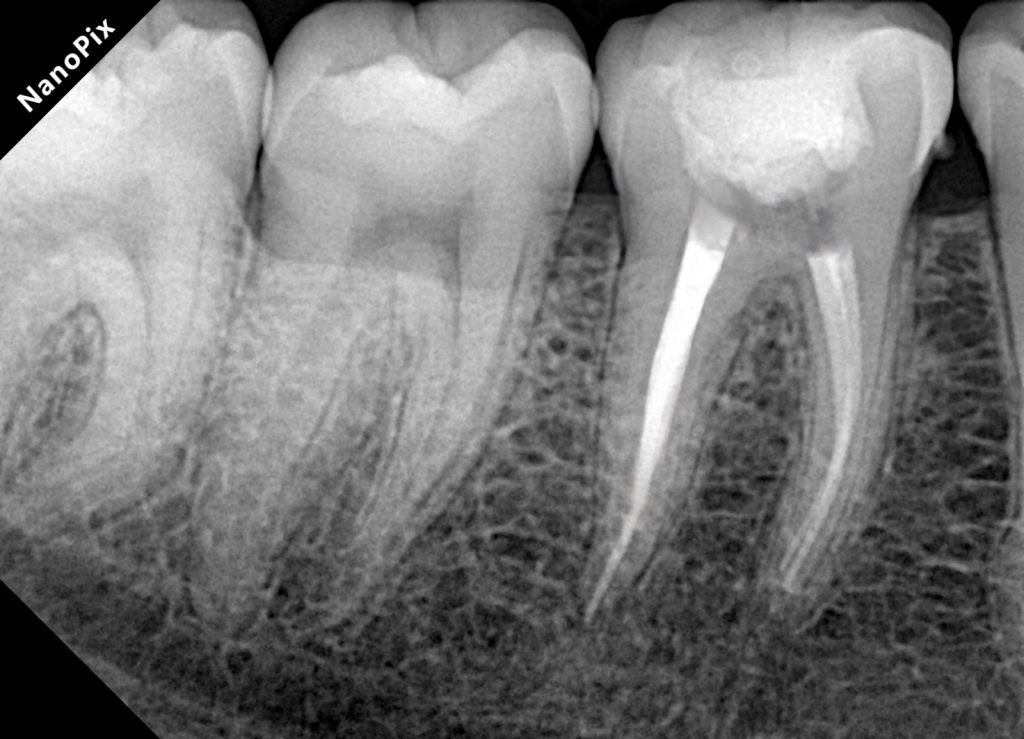

Obturation Using Warm Vertical Compaction

Following thorough cleaning and drying, obturation was completed using warm vertical compaction. Thermoplasticized gutta-percha allowed for intimate adaptation to canal walls, isthmuses, and apical complexities, providing a dense, homogeneous three-dimensional seal. Post-obturation assessment confirmed appropriate length control and obturation density.

Outcome and Prognosis

The final restoration demonstrated proper occlusal form, functional harmony, and a secure coronal seal. Radiographic evaluation confirmed stable obturation without signs of periapical pathology. By integrating endodontic and restorative phases into a single biologically driven workflow, the tooth was returned to function with an optimized long-term prognosis.